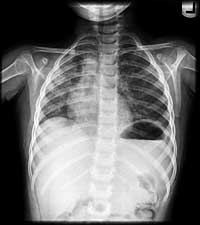

YOU CAN REVIEW THE CXR FROM HER INITIAL FLU-LIKE ILLNESS TWO MONTHS AGO AND COMPARE IT TO HER CURRENT CXR.

Repeat

of March 22 (with initial flu-like illness) for review

May

22 (current exam)

Two

other intervening CXR's are also reviewed and you confirm that her radiologic

imaging shows migrating patchy opacifications (initially worse on the

left and now worse on the right), which appear like "ground glass" on

the current CXR, and show a mixed airspace/interstitial pattern and low

lung volumes.